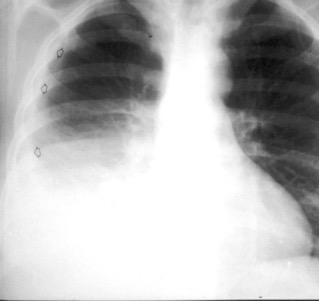

Neumonía a neumococos base izda. con derrame que aumenta.

Broncograma en lateral y en US.

(36-66% en ingresados)